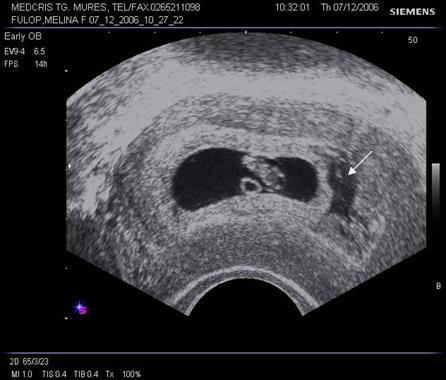

Fig nr 6 Decolare de pol inferior ( cu sageata ) la o sarcina de 7 sapt

Fig. nr. 66. Aceeasi sarcina, ca in figura precedenta, la 12 saptamani , fara imagini patologice la polul inferior ovular, marcat cu sageata